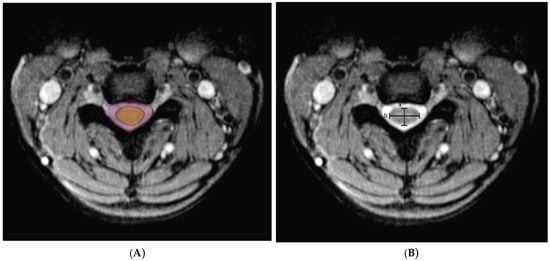

8. Imaging